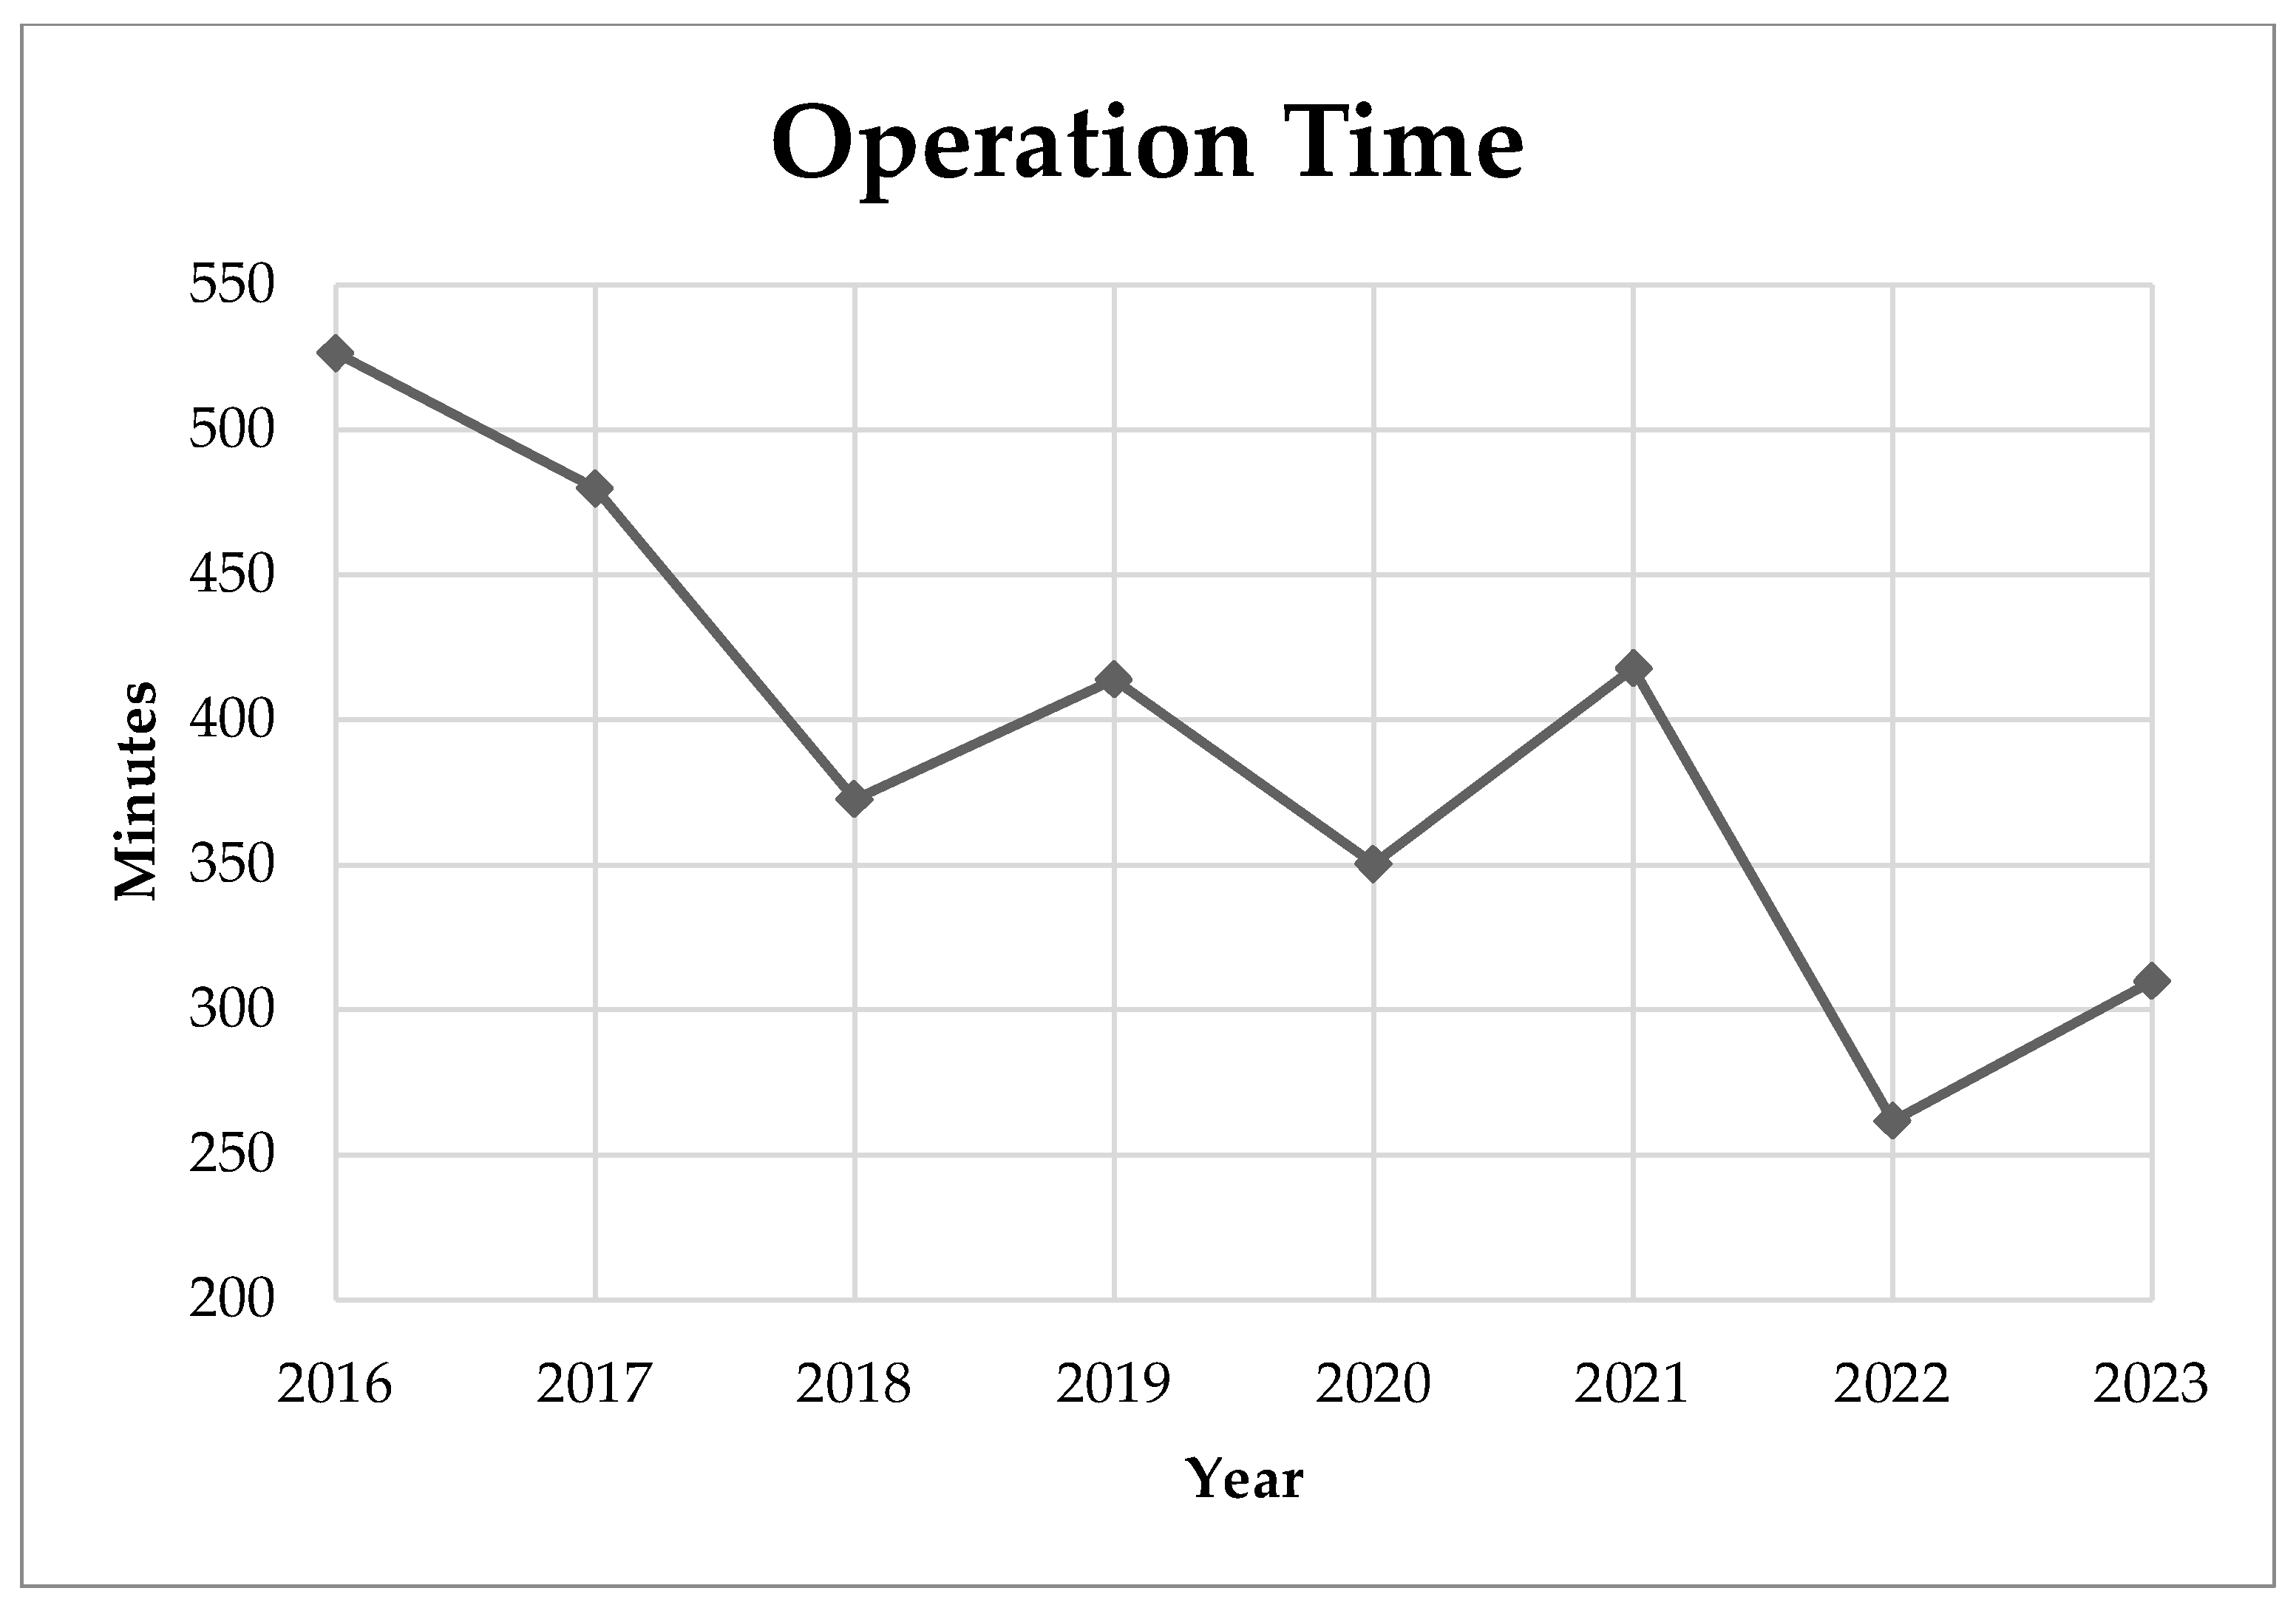

3. Results

4. Discussion